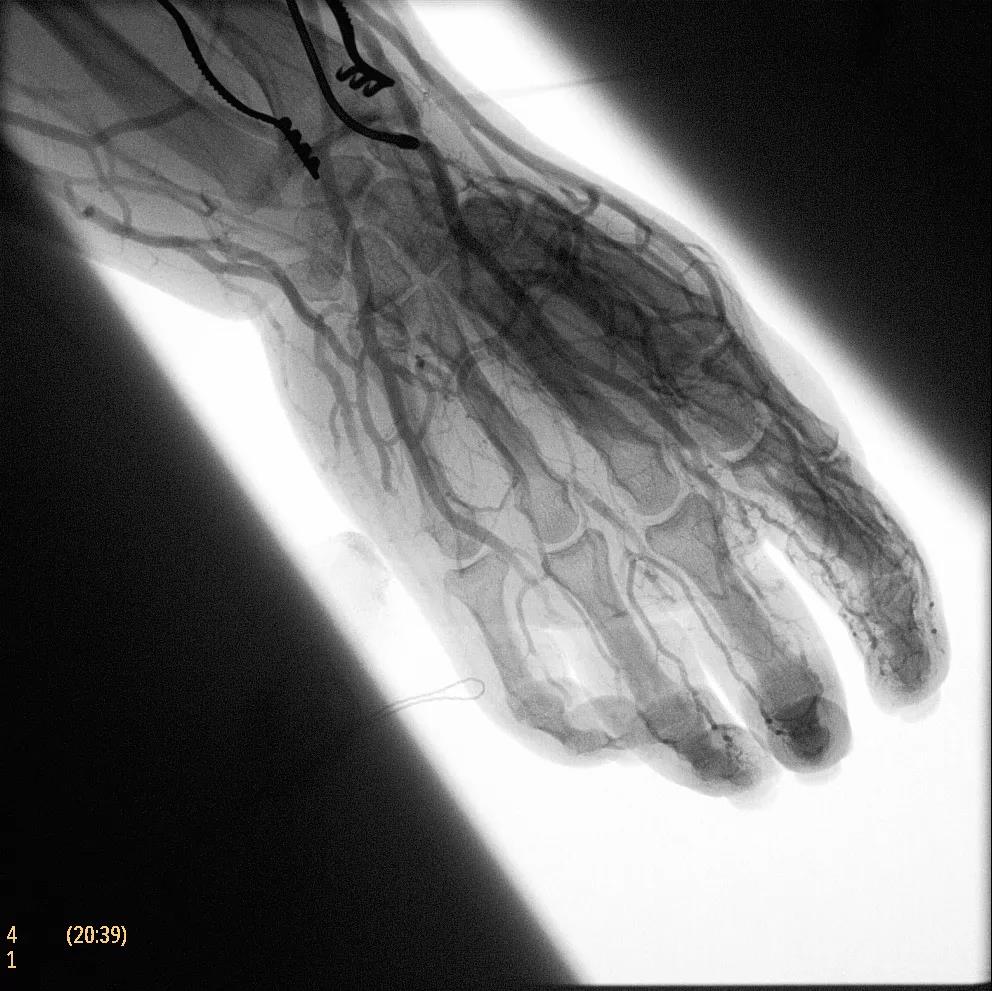

為了獲得清晰的高質(zhì)量圖像,Zenition 70 采用了與公司Azurion平臺(tái)相同的圖像處理算法,可提供患者解剖結(jié)構(gòu)的高清可視化和更大的可視區(qū)域。飛利浦的MetalSmart軟件等功能可確保圖像質(zhì)量,該軟件可自動(dòng)調(diào)整圖像的對比度和亮度,以便在視野中存在金屬物體(如植入物)時(shí)提高圖像質(zhì)量 - 這一特性使Zenition 70在整形外科中特別有用。